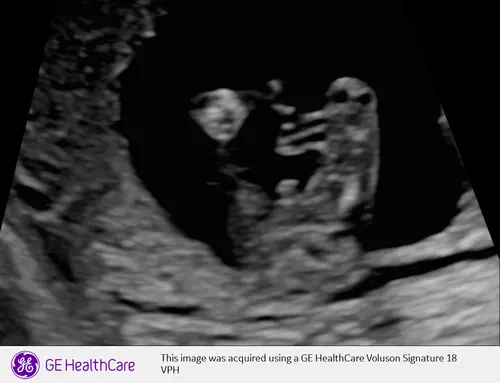

Meisje

Door die twee streepjes, toch? Chatgpt zegt dat het een uitsteeksel is, en zegt vermoedelijk een jongen, dus ik twijfel enorm, maar mij lijkt het ook een meisje. Dankjewel voor het meekijken.

Ja vermoed ik wel, anders zou je daar balletjes moeten zien met 18 weken. Voor het mooie moet het beeld iets meer naar voren zijn, maar chatgpt heeft het vaker fout dan goed🤣